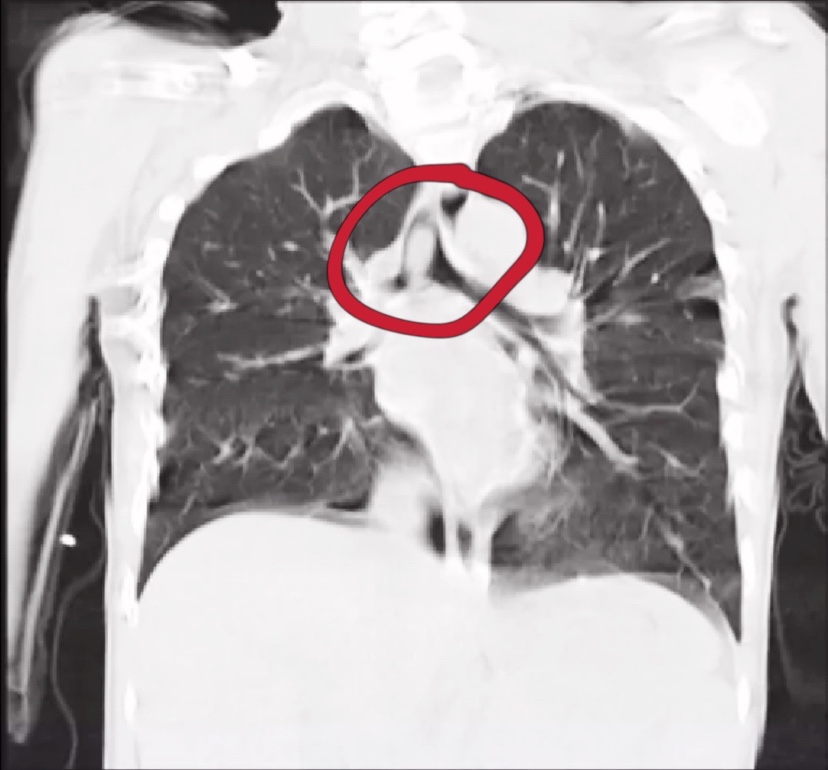

气管及右侧主支气管被堵住

儿童耳鼻喉科团队立即给孩子施行了支气管镜下异物取出术。术中看到,患儿的右侧主支气管及左侧的部分支气管被异物堵住,血氧饱和度也极不稳定,在麻醉医生的密切配合下,钟建文主任医师凭借丰富的经验快速将异物取出,孩子转危为安。